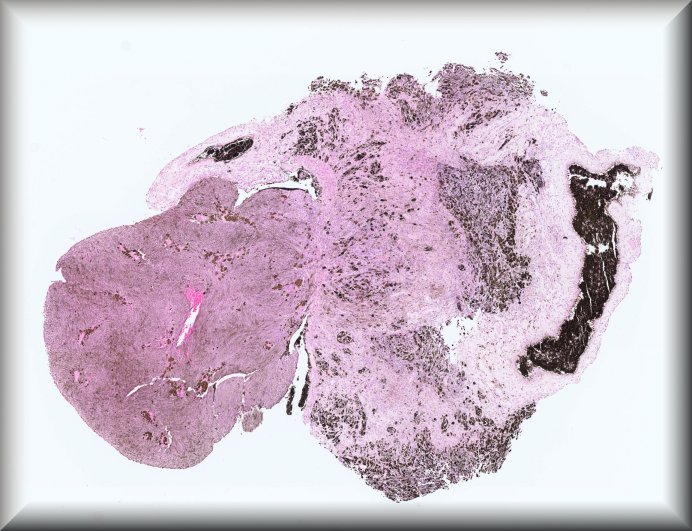

Fiona Roberts (Glasgow): 9 year old female with buphthalmos secondary to congential glaucoma. Protocol |